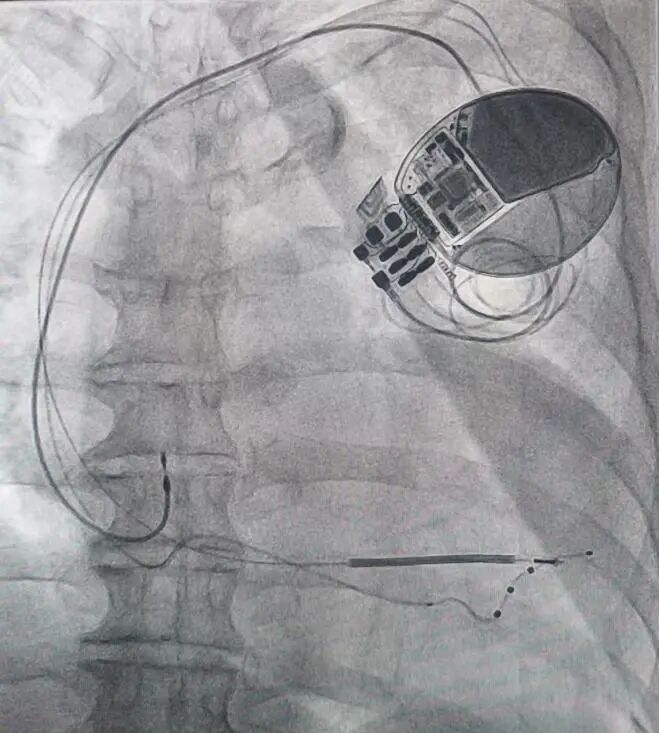

这一手术在起搏领域难度系数极高,需要操作者熟练掌握起搏器植入技术及冠脉诊疗技术。心血管内科二病区团队凭借丰富的临床经验与精湛技术,通过腋静脉穿刺,将三根电极精准植入右心房、右心室及左心室侧壁,耗时2小时完成设备植入。

(▲医务人员成功为王女士植入CRT-D)